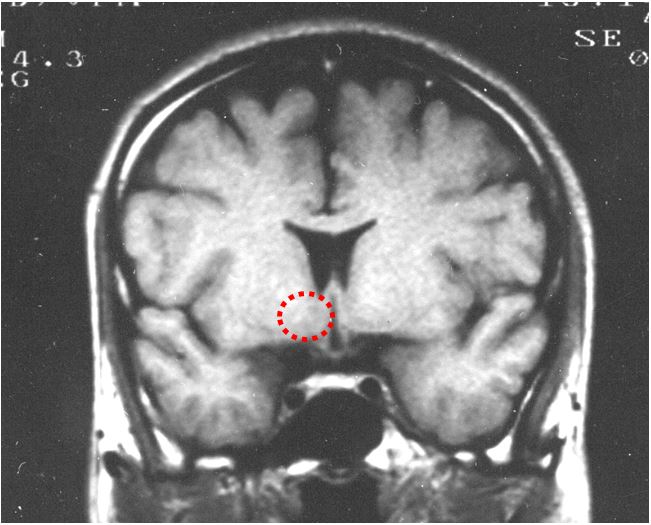

では免疫系はどのようにして、これらの症状を引き起こすのでしょうか?ウィルスを検知した免疫系の細胞(白血球)はサイトカインと呼ばれる警戒信号物質を放出します。それが血液循環によって全身に運ばれ、脳にも作用します(図1)。サイトカインが脳の血管の細胞に作用し、そこから新たな物質が脳に放出されます。そしてその物質が発熱中枢に作用することで発熱や痛みが起こることを、私は明らかにしました(図2)。しかし、食欲不振やだるさなどの他の症状は、発熱と同じ仕組みでは説明できず、不明な部分が残されています。